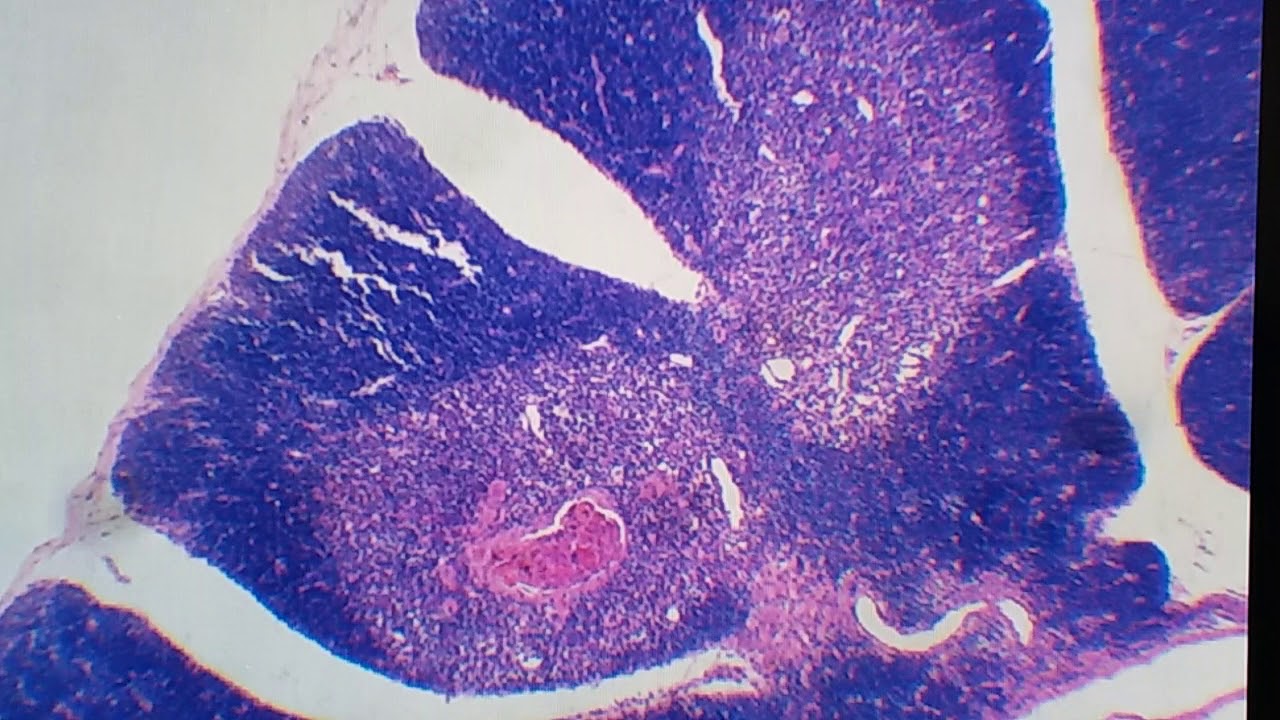

se comunica com a cavidade oral então o jornal e ela língua faringe com a laringe beleza Colarinho de laranja e o que acontece todos têm essas três regiões que são separados um critério que se comunica com estruturas diferentes Neva do corpo da cabeça principalmente a laringofaringe do pescoço já e também porque elas são revestidas por bactérias diferentes algum observar aqui como é que ele só então aqui tão as três regiões da faringe E a nasofaringe agora estou começando na área da Psicologia nasofaringe ela vai ter um revestimento de epitélio respiratório quando temos criatório né naquele

bulli tão lá que o epitélio colunar se elas cumpridas e seus plastificar o pseudo-estratificado ou seja ele tem cara de certificado mas não é eu falso estratificada Na verdade ele simples que todas as células só cão a lâmina basal eu fiz dois vídeos gente então só de creme depilatório Então tá tudo lá as características desse esperta ela tem várias células de defesa importantes que você localize forme produtor de murro E além disso então ele colunar pseudoestratificado e ciliado porque as telas com mais apresentam cílios que apresenta o que movimento esse movimento unidirecional esse movimento é

tem carro desclassificado por isso que a gente sabe o nome difícil de praticar então ele pele assim frágil tá uma vassourinha né a orofaringe e laringofaringe elas vão ser revestidos pelo mesmo critério tá então essa parte Rosa todinha ele respiratório daqui para baixo a gente vai ter o epitélio pavimentoso estratificado não queratinizado se nome menso né de nobreza histológica então isso pele e aquele critério velho de guerra onde as células são todas achatadas e aqui são várias camadas de células achatadas então por isso que ela não espere para comer Tozzo se ela chapada e notificado